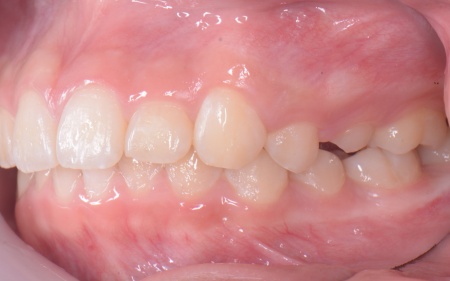

| カウンセリング | 拝見したところ、上の犬歯が歯列の外側に飛び出すように生えている、いわゆる八重歯でした。 さらに、上下の歯全体がデコボコに生えている「叢生(そうせい)」と呼ばれる状態で、これは歯が正しい位置に並ぶためのスペースが不足していることが原因だと考えられます。 このまま放置して顎の成長が完了してから矯正治療を行う場合、歯を並べるスペースを確保することが難しく、永久歯を抜く処置が必要になるケースがあります。 以上のことから、今の段階で歯並びを整える治療が必要だと診断しました。 |

患者様のご家族は「将来的な抜歯はできるだけ避けたいので、今のうちに治療をしたい」と希望されたため、成長期の段階で歯列を広げ、歯が並ぶスペースを確保する小児期の矯正治療「1期矯正」を提案しました。

メリット デメリット また、治療にあたりお口全体のバランスを確認したところ口元の突出はなく、顎のサイズはやや小さめですが、成長期であることから歯列の拡大が可能な状態だと判断しています。 以上の内容について丁寧に説明し、治療に同意いただきました。 まず、上顎に顎の骨を広げるための固定式の矯正器具「急速拡大装置」を、下顎には歯並びの幅を広げるための「リンガルアーチ」を装着します。 次に歯の位置を整えるため、ワイヤー矯正を開始します。 最後に、歯並びが整って見た目や噛み合わせにも問題がないことを確認し、装置を取り外して第1期矯正治療を終了しました。 現在も経過観察を継続していますが、歯が元の位置に戻る後戻りも見られず、残っている乳歯から永久歯への生え変わりも順調に進んでいます。 |